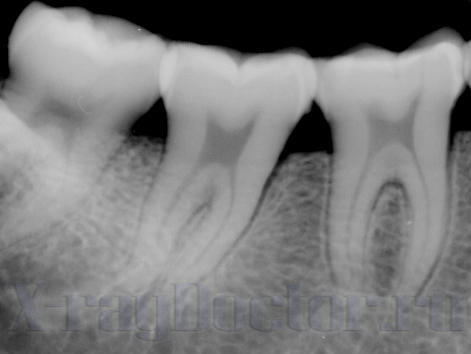

Как увидеть пульпит и кариес на рентгеновских снимках

Пульпит на снимке определяется затемнением в центральной и нижней части зуба. Заболевание характеризуется воспалительными